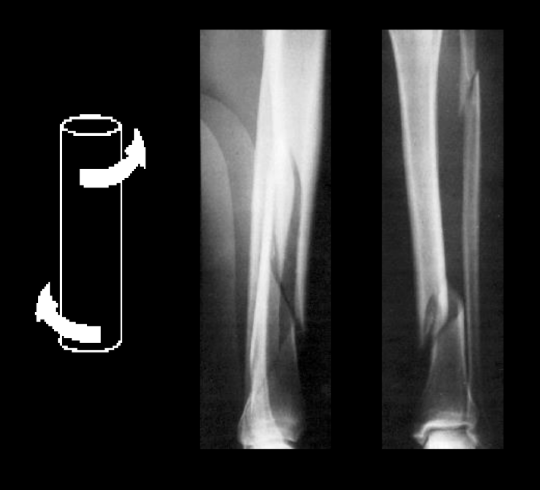

torsion load will cause spiral and tibia fractures which heal (faster//slower) than some transverse fractures. why?

faster!

more surface area and less soft tissue damage → low load injury